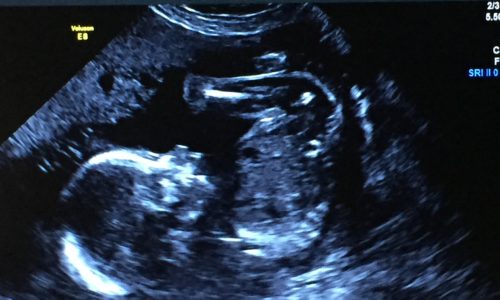

At Kristy Isert’s routine 20-week ultrasound, doctors discovered something was wrong with her baby’s heart. Further testing confirmed Otto had complex congenital heart defects, conditions that could put his life at risk without specialized care.

Kristy was referred to the Royal Alexandra Hospital, where maternal-fetal medicine specialists and pediatric cardiologists worked together to closely monitor Otto’s heart in utero. Advanced imaging, frequent scans, and coordinated care helped prepare for a high-risk delivery and the cardiac care Otto would need immediately after birth.